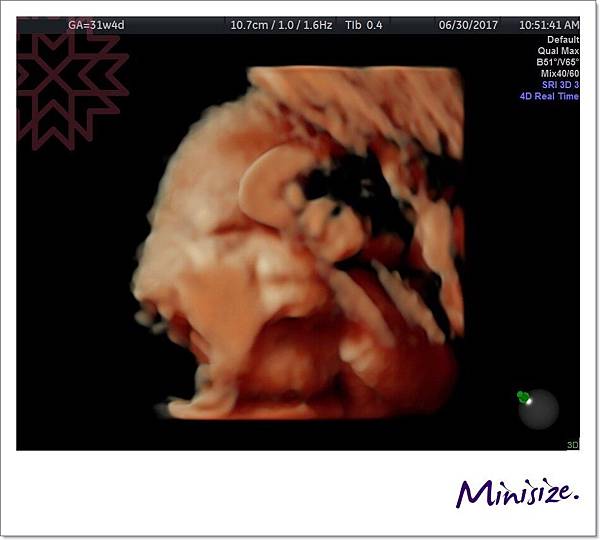

31週時

第一次看到Timo睜開雙眼

經驗豐富的醫生也驚嚇地說她很少看到寶寶眼睛張這麼大

後來 Timo又躲起來

醫生搖肚皮搖好久後

正當麻麻跟醫生、護士聊天

說到寶寶好像都知道產檢的時候會被超音波偷拍

不想要自己的隱私被打擾!

麻麻還說是偶像包袱嗎?

Timo立馬用「偷瞪」的表情回應我們

哈哈哈哈哈

這怪表情把我們都逗樂了~

最後

Timo秀出愛睏想睡覺的表情

我們就不打擾他了